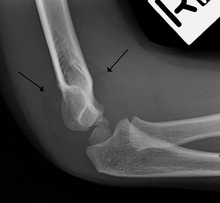

Anterior sail signs as well as posterior fat pad in a child with a supracondylar fracture.

On an elbow X-ray, the fat pad sign, also known as the sail sign, suggests an occult fracture. Its name derives from the fact that it has the shape of a spinnaker (sail).[1] It is caused by displacement of the fat pad around the elbow joint. Both anterior and posterior fat pad signs exist, and both can be found on the same X-ray.

In children, a posterior fat pad sign suggests a condylar fracture of the humerus. In adults it suggests a radial head fracture. The fat pad sign only occurs after an intra-articular fracture.

The posterior fat pad is normally pressed in the olecranon fossa by the triceps tendon, and hence invisible on lateral radiograph of the elbow.[3] When there is a fracture of the distal humerus, or other pathology involving the elbow joint, inflammation develops around the synovial membrane forcing the fat pad out of its normal physiologic resting place. This is visible as the "posterior fat pad sign" and is often the only visible marker of a fracture, particularly in the pediatrics population.